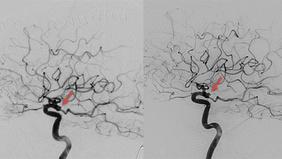

Mission: Impossible - An acom aneurysm with almost no access

By Jose De Jesus GUTIERREZ-BAÑOS

Published on February 24, 2026